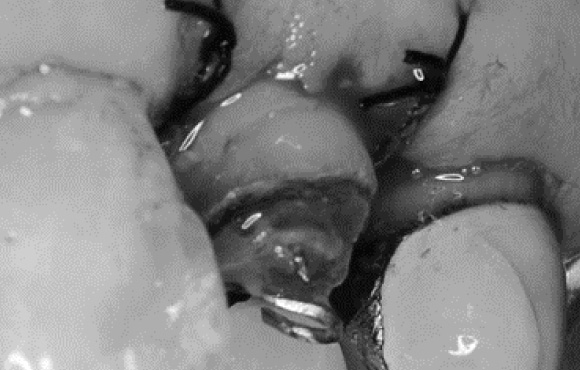

虫歯が深くこのままでは冠が入れられません。

ゴムで引っ張り上げることで歯茎の中から歯の健全な部分を露出させ被せ物で処置することが可能になります。

①歯が深くこのままでは適切に被せ物ができません。ゴムで歯歯茎の中に埋まっている健全な歯質を出してきています。

②二か月ほどでゴムの力をかけ2mmから3mm牽引しました。